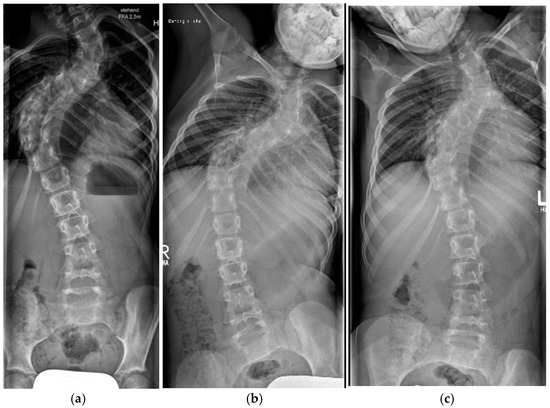

3.3.5. Halo-Gravity Traction

3.3.6. Bone Grafting

5.1. Cervical Spine